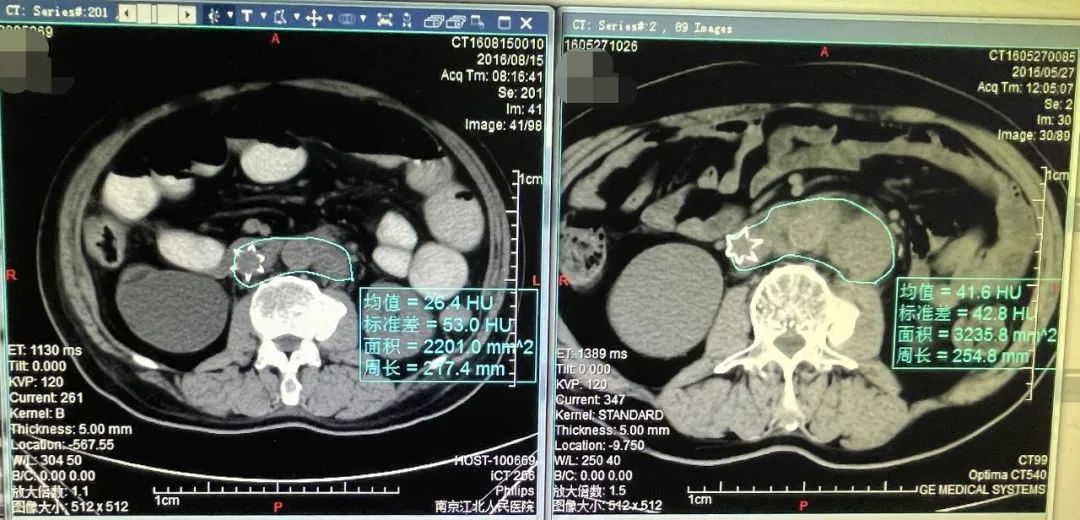

伽马刀就是利用射线照射垂体瘤达到治疗目的,其副作用较低,每组射线

图片尺寸821x466